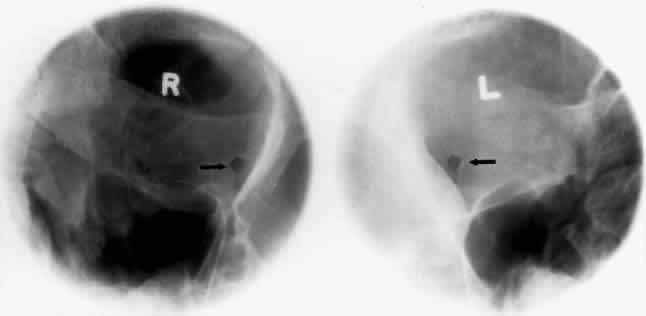

OPTIC FORAMEN (RHESE POSITION)

In 1911 Rhese14 described a projection (Fig. 6) for the evaluation of the ethmoid sinuses and the optic foramen. The patient is positioned with the orbit to be studied against the x-ray cassette. The zygoma, nose, and chin should touch the cassette. The x-ray beam is directed posterior-anteriorly at 40 degrees to the midsagittal plane.5,6 In this position the optic canal is in the inferolateral quadrant of the orbit and oriented perpendicular to the x-ray cassette.15 Variations of this standard position can be used to view other structures of interest. The Rhese projection allows assessment of the orbital apex, in particular, the optic foramen, optic strut, and the upper ethmoid sinus. A pneumatized anterior clinoid process may simulate the optic foramen. The landmark for finding the foramen is to find the planum sphenoidale; the optic foramen lies at its lateral end. The optic canal may be evaluated for expansion or compression by disease processes, such as optic nerve tumors (glioma and meningioma) and trauma. CT and magnetic resonance imaging show much better detail and therefore have replaced the use of plain films for evaluation of the optic canal.

Fig. 6. A and B. Schematic showing positioning for an oblique apical projection (Rhese position). (CR, central ray; CM, canthomeatal line) C. Radiograph of an oblique apical projection. (a, right optic canal; b, optic strut; c, superior orbital fissure; d, ethmoid sinus; e, planum sphenoidale; f, greater wing of sphenoid) (A and B; Rao VM, Gonzalez CF: Plain film radiography and polytomography of the orbit. In Gonzalez CF, Becker MH, Flanagan JC [eds]: Diagnostic Imaging in Ophthalmology, pp 1–7. New York, Springer Verlag, 1986)